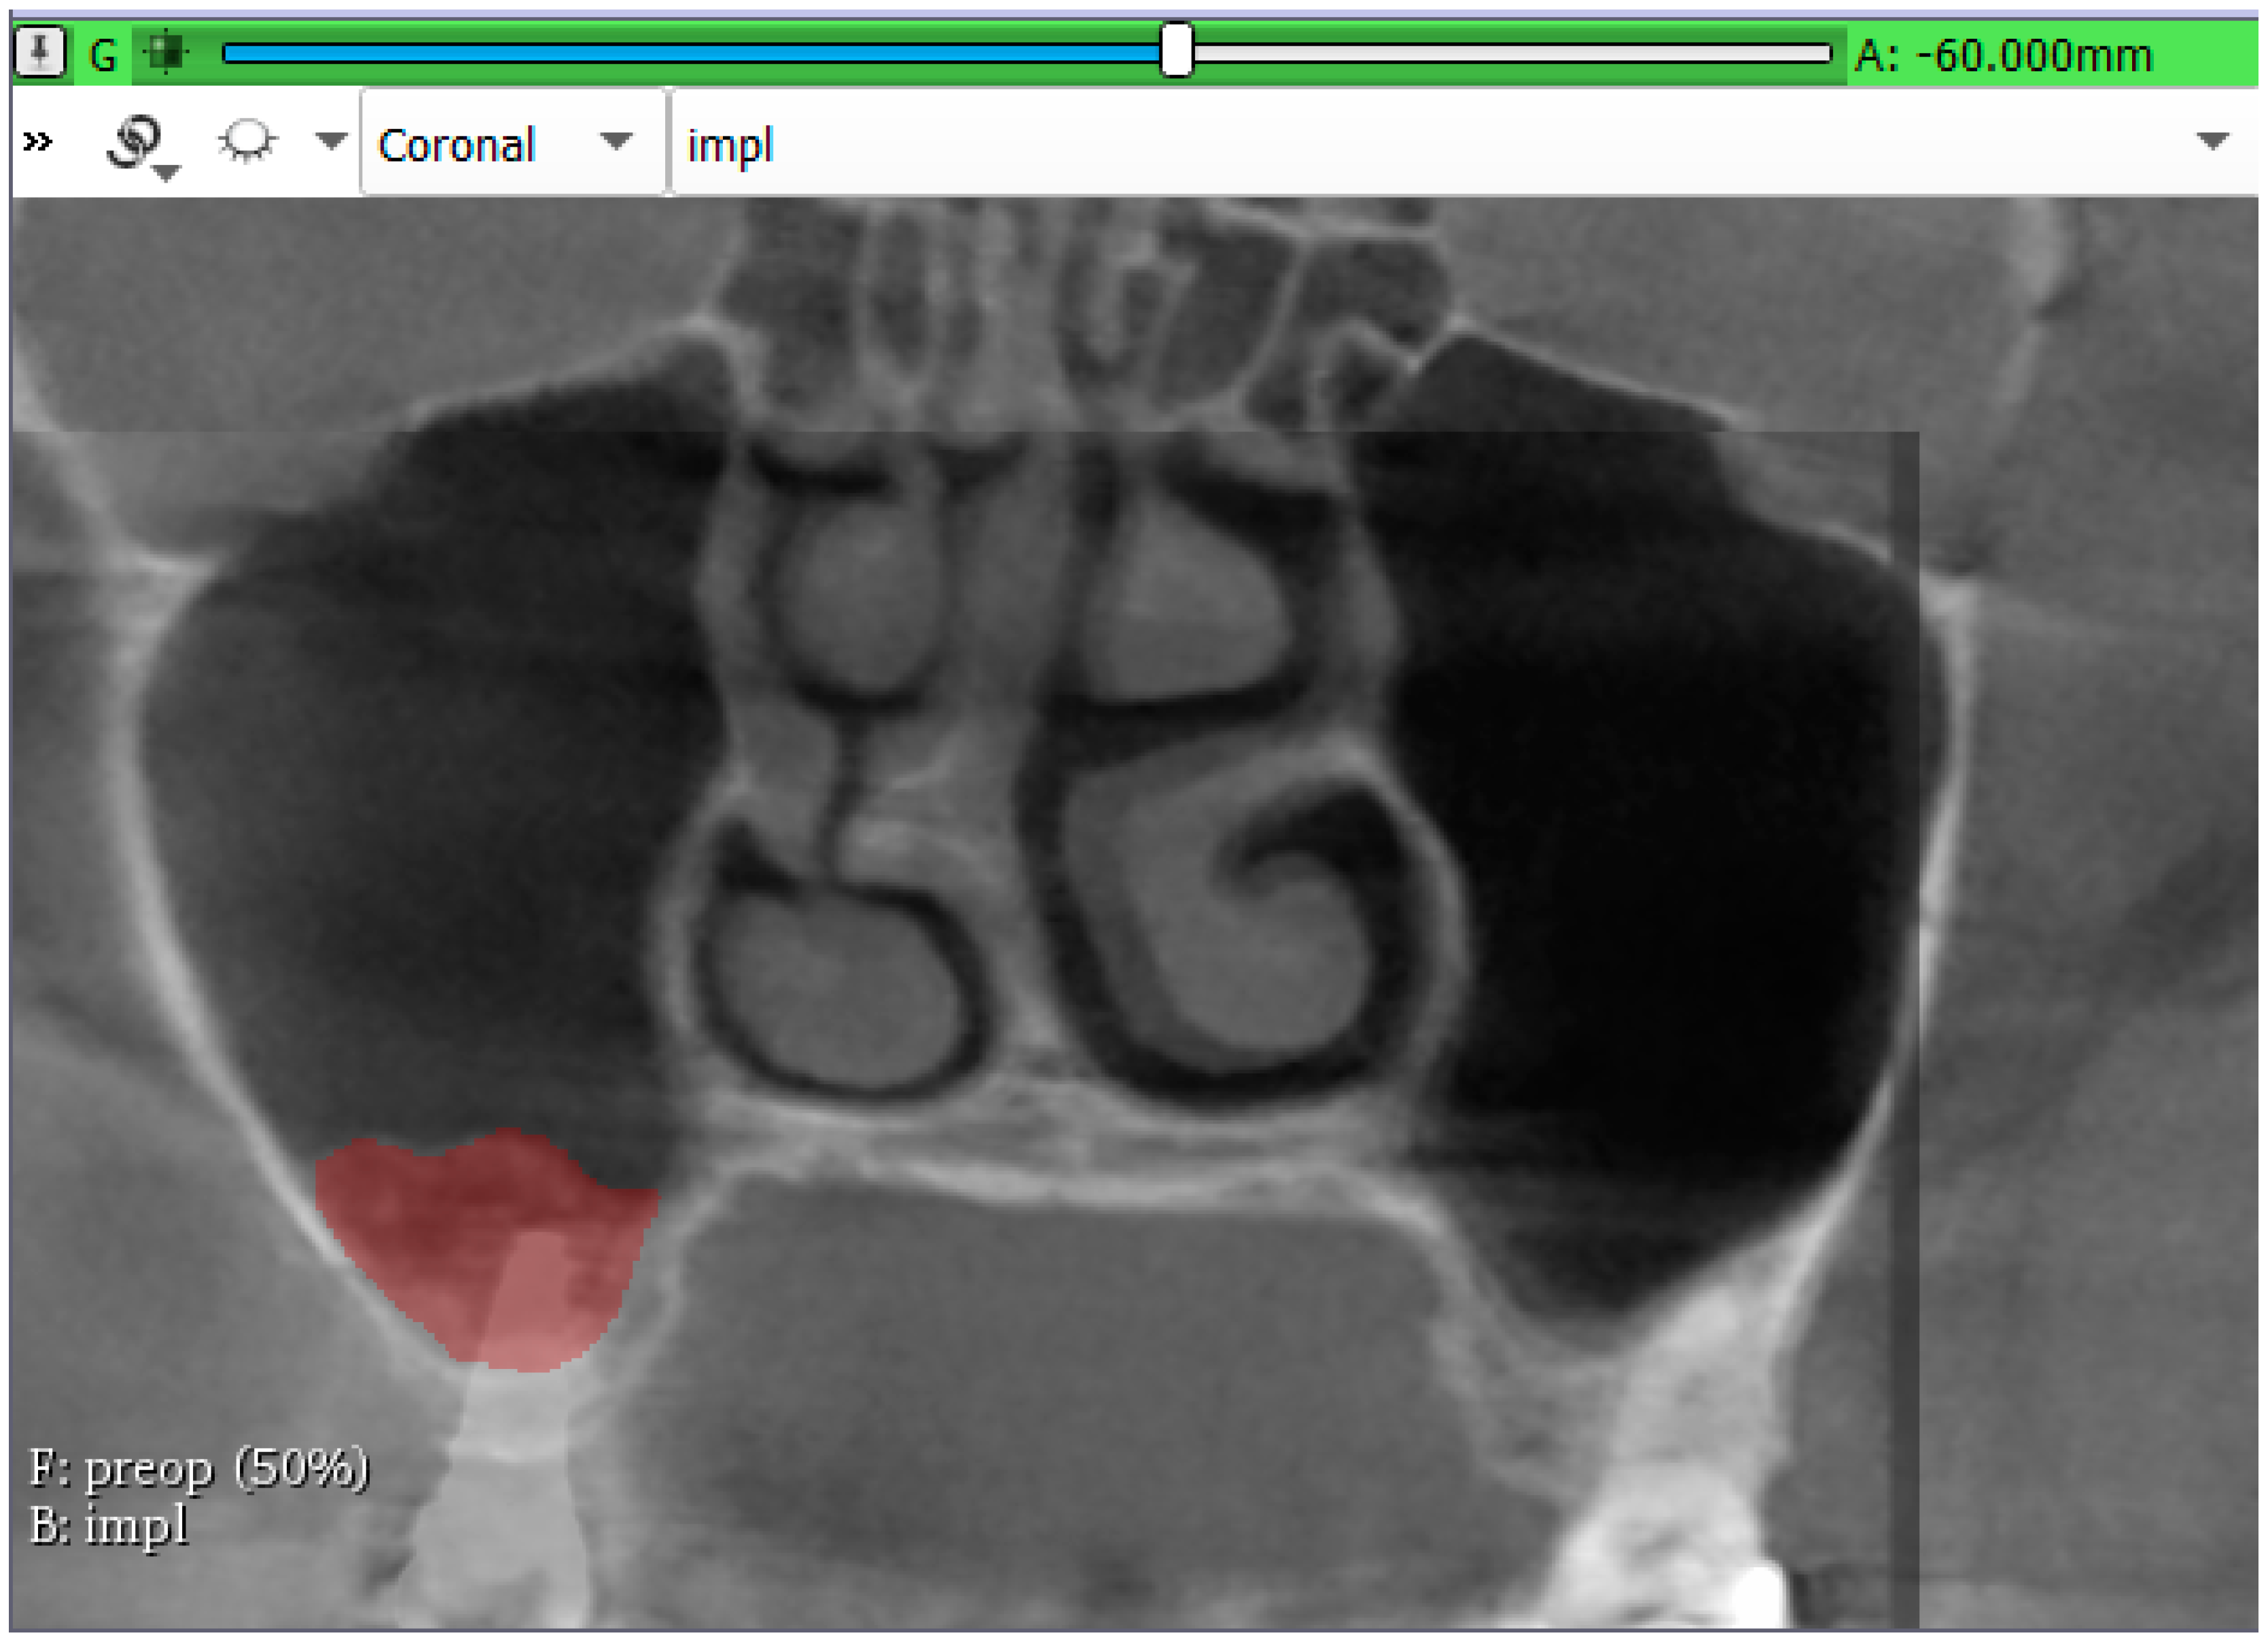

3.2. Volumetric Assessment of the Augmented Sinuses

| Bone gain after 6-months | mm3 | 1623.32 | 815.79 | 2330.43 |

| Bone gain after 3-years | mm3 | 981.19 | 371.89 | 1403.69 |

| Volume reduction | % | 39.28 | 11.88 | 61.02 |